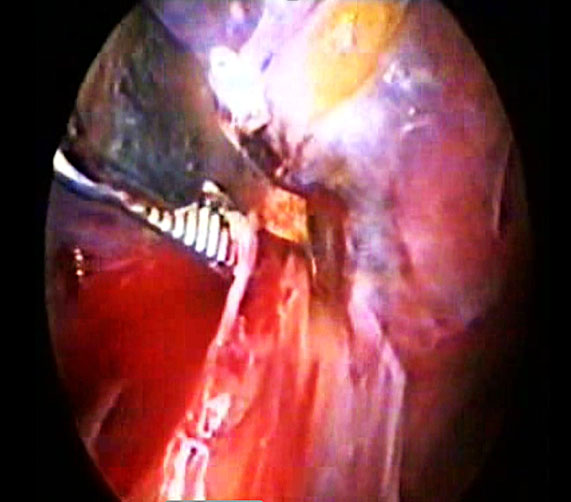

During sacral colpopexy, the left common iliac vein (Figure 18) may be inadvertently punctured by a needle. In such cases, it is best to apply pressure using two gauze pads placed perpendicularly for 5–10 minutes. Once the bleeding stops, a small retroperitoneal collection is usually self-limiting.

|

(a) |

(b) |

18

(a) Needle-tip puncture injury of left common iliac vein in the presacral region. (b) Two good sized gauzes held with atraumatic forceps applying proper pressure for 10 minutes on the vein. (c) On removal of the gauze there is no active bleeding, a residual static collection is seen.